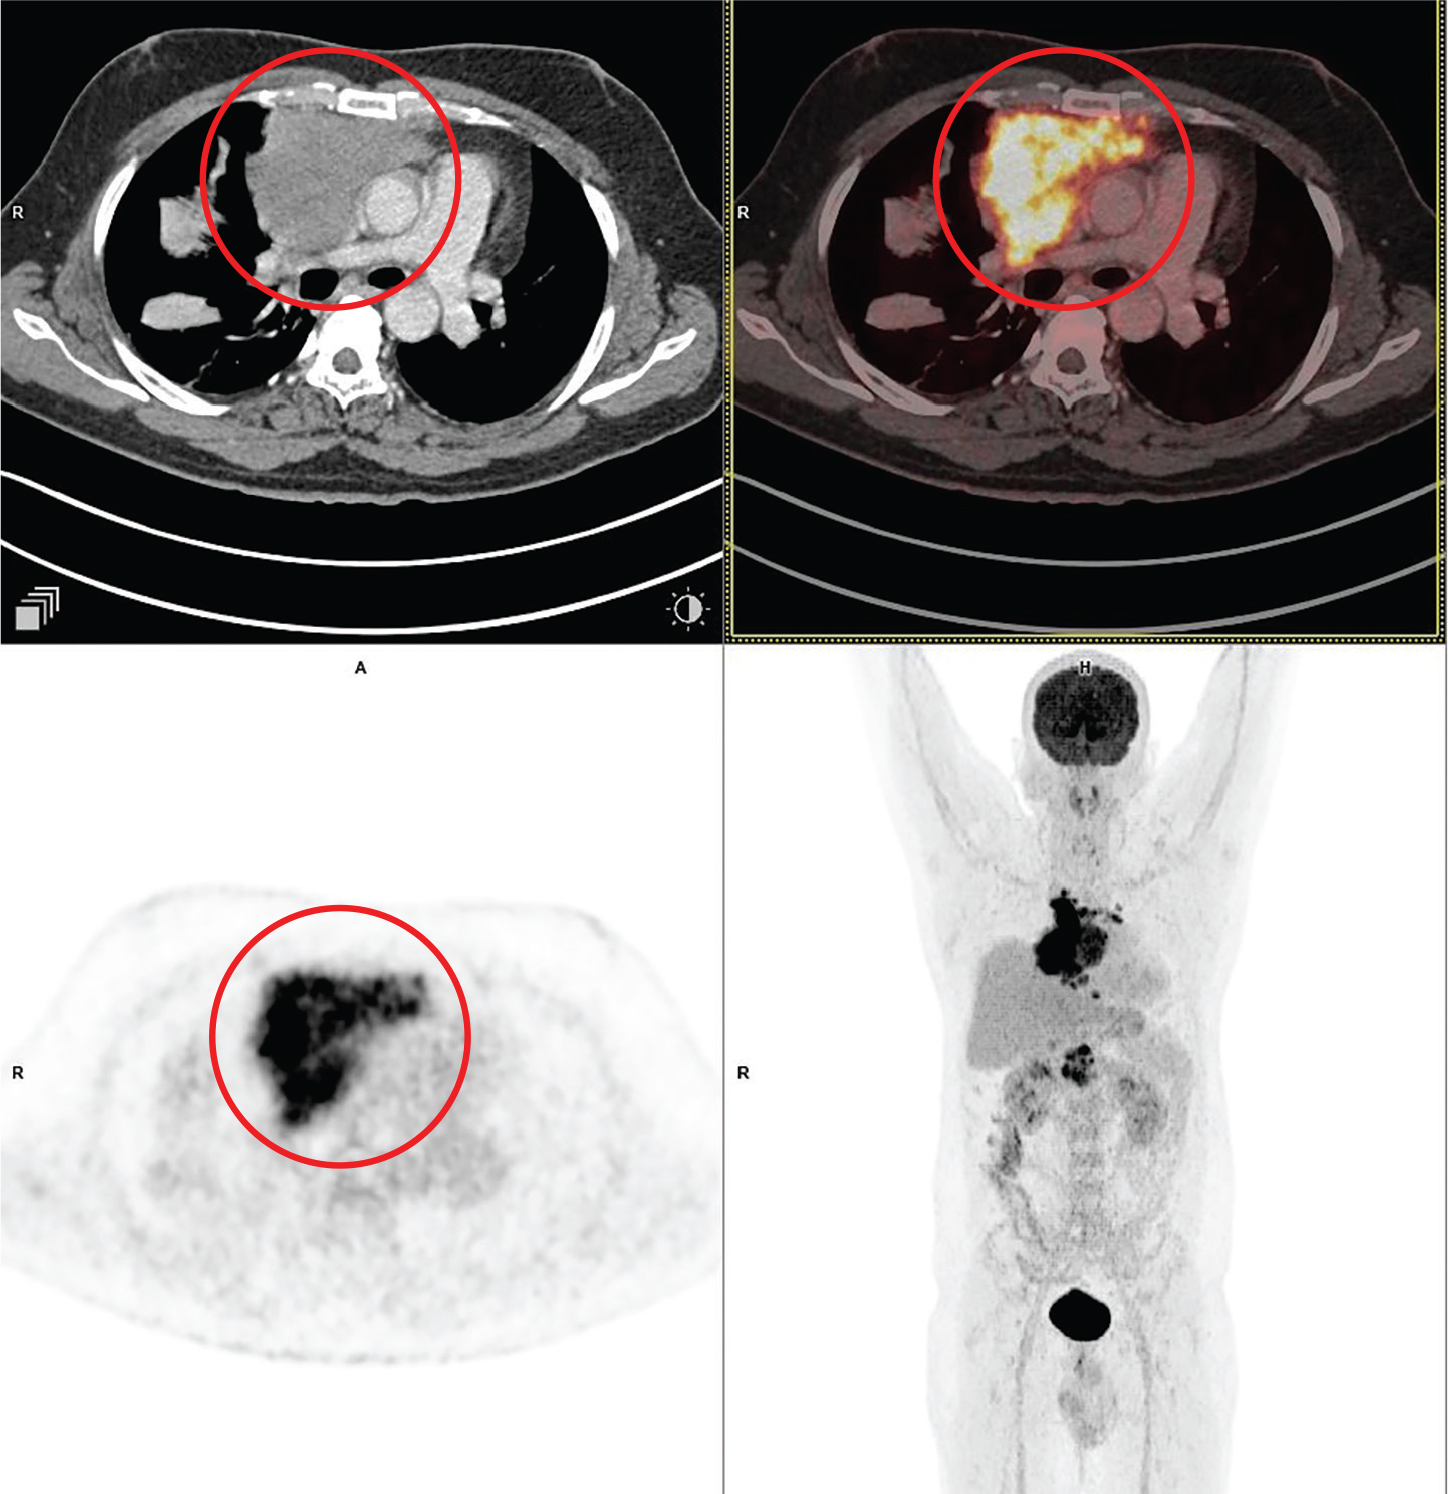

Fig 6

Figure 6. Posterior mediastinal mass that was pathologically confirmed as neuroblastoma. 68Ga - dotatate PET/CT images include axial CT (top left panel), fused axial PET/CT (top right panel), axial PET (bottom left panel), and maximum intensity projection (MIP) PET image (bottom right panel). In the red circle, a large lobulated heterogeneously 68Ga - dotatate avid and enhancing mass is seen involving the left chest cavity and posterior mediastinum with contiguous extension across the midline, and into the superior midline retroperitoneal / posterior abdominal cavity regions. There was additional 68 Ga - dotatate avid mass involving the paranasal sinuses, orbits, nasal cavity, facial bones and multiple other sites of skeletal involvement (not on the included PET/CT images and could be appreciated on the MIP image) that were suggestive of metastatic disease.